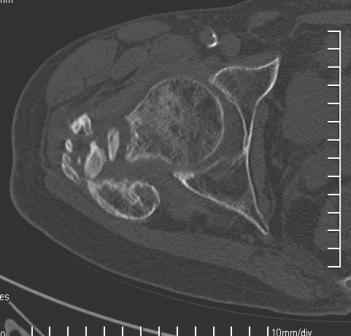

Уважаемый Глеб, боли из-за ложного сустава шейки бедра. Сращения там нет.

Тазобедренный сустав сохранный и возраст пациента позволяет побороться. Согласен с Максимом, попробуйте остеотостеотомию.

Уважаемый Глеб! Укорочение наверное побольше, да и наружно-ротационная установка скорее всего присутствует. Суставная щель прекрасная, головка живее всех живых. Ратую за подвертельную с латерализацией: исключает нарушение механической оси («исключает вальгус в коленe»), максимально удлиняет без натяжения m.iliacus. Для иллюстрации остеотомия-переделка (слава богу не автопеределка) у мужчины 65 лет.

Филипчук.

PS. Извините за качество последнего снимка, рентгенограмма выполнена по м. жительства, там где был проведен синтез. Последний снимок выполнен через 2 мес. п\о, больной без разрешения начал наступать, слава богу все обошлось.